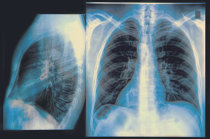

A radiografia baseia-se no fato de que o feixe de raios catódicos emitidos por uma ampola de raios X (por isso a radiografia é também chamada de Raios X) pode atravessar de modo diferente os diversos tecidos orgânicos e atingirem uma película (“filme”) a eles anteposta, gerando imagens. Como esses raios atravessam com mais facilidade as partes aeradas e os tecidos moles do corpo (de menor densidade), chegam ao filme com maior intensidade e o impressionam mais fortemente na projeção desses órgãos, gerando registros mais escuros. Os tecidos mais densos, como os ossos, por exemplo, os retém mais e eles chegam ao filme com menor intensidade e geram, na projeção desses órgãos, registros mais claros. Assim, depois de revelados, os filmes mostram imagens dos órgãos em diferentes tons de cinza. Na verdade, as imagens projetadas correspondem a áreas de sombra dos raios X emitidos.

As radiografias são utilizadas em muitas situações médicas diferentes. No exame dos ossos elas podem diagnosticar fraturas, tumores, distúrbios de crescimento e de postura, osteoporose8, entre outras coisas. Nos pulmões9 podem detectar de pneumonia10 ao câncer11, passando por várias patologias e por sinais12 indiretos de afecções13 em outros órgãos (sobretudo no coração14). Por outro lado, pode localizar corpos estranhos ou outros objetos que hajam penetrado os pulmões9 (lâminas, projéteis, etc.). Os dentistas geralmente a usam para descobrir cáries15 e fraturas dos dentes ou para estudar o interior e as raízes dos dentes. Associada a contrastes, a radiografia permite diferenciar tecidos de características bem similares, tais como os músculos16 e vasos sanguíneos17, por exemplo, e serem empregadas em estudos como o das vias urinárias.